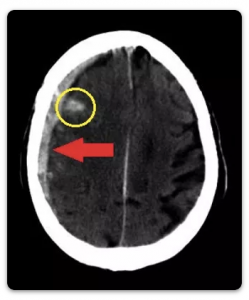

Subdural Hematom (Kanama): Beyin zarı (dura) ile beyin arasında gelişen kanamalardır. Yani kanama direkt olarak beyinle temas halindedir. Epidural hematomlardan daha sık görülürler. Özellikle ağır kafa travmalı olgularda görülme sıklığı %30’dur. Kanama genellikle beyin ve beyin zarı (dura) arasındaki köprü damarların travma anında kopmalarından kaynaklanır. Eğer travma çok ağırsa, bu durumda direkt olarak hasar görmüş beyin dokusunun kanamasına bağlı da olabilir. Bazen (ileri yaşlarda, alkol kullananlarda, kan sulandırıcı ilaçlar kullanan hastalarda daha sık) kafaya alınan hafif darbelerden haftalar hatta aylar sonra dahi subdural hematom gelişebilir. Buna kronik subdural hematom denir. Akut (travmadan hemen sonra gelişen) subdural hematomun sonuçları epidural hematomlardan çok daha kötüdür. Bunun en büyük nedenlerinden biri, bu kanamaların sıklıkla beyin yaralanması ile birlikte görülmesidir. Subdural hematomlardaki yüksek ölüm oranı, hızlı cerrahi müdahale ve agresif yoğun bakım tedavisi ile düşürülebilir. Subdural hematom zmeliyatı epidural hematomlarınkiyle benzerlik gösterir. Farklı olarak, kanama beyin zarının altında olduğundan bu zar da kaldırılır ve kanama boşaltılır. Yani beyin ile direkt temas vardır. Bu da ameliyata bağlı komplikasyon ihtimalini arttırır.